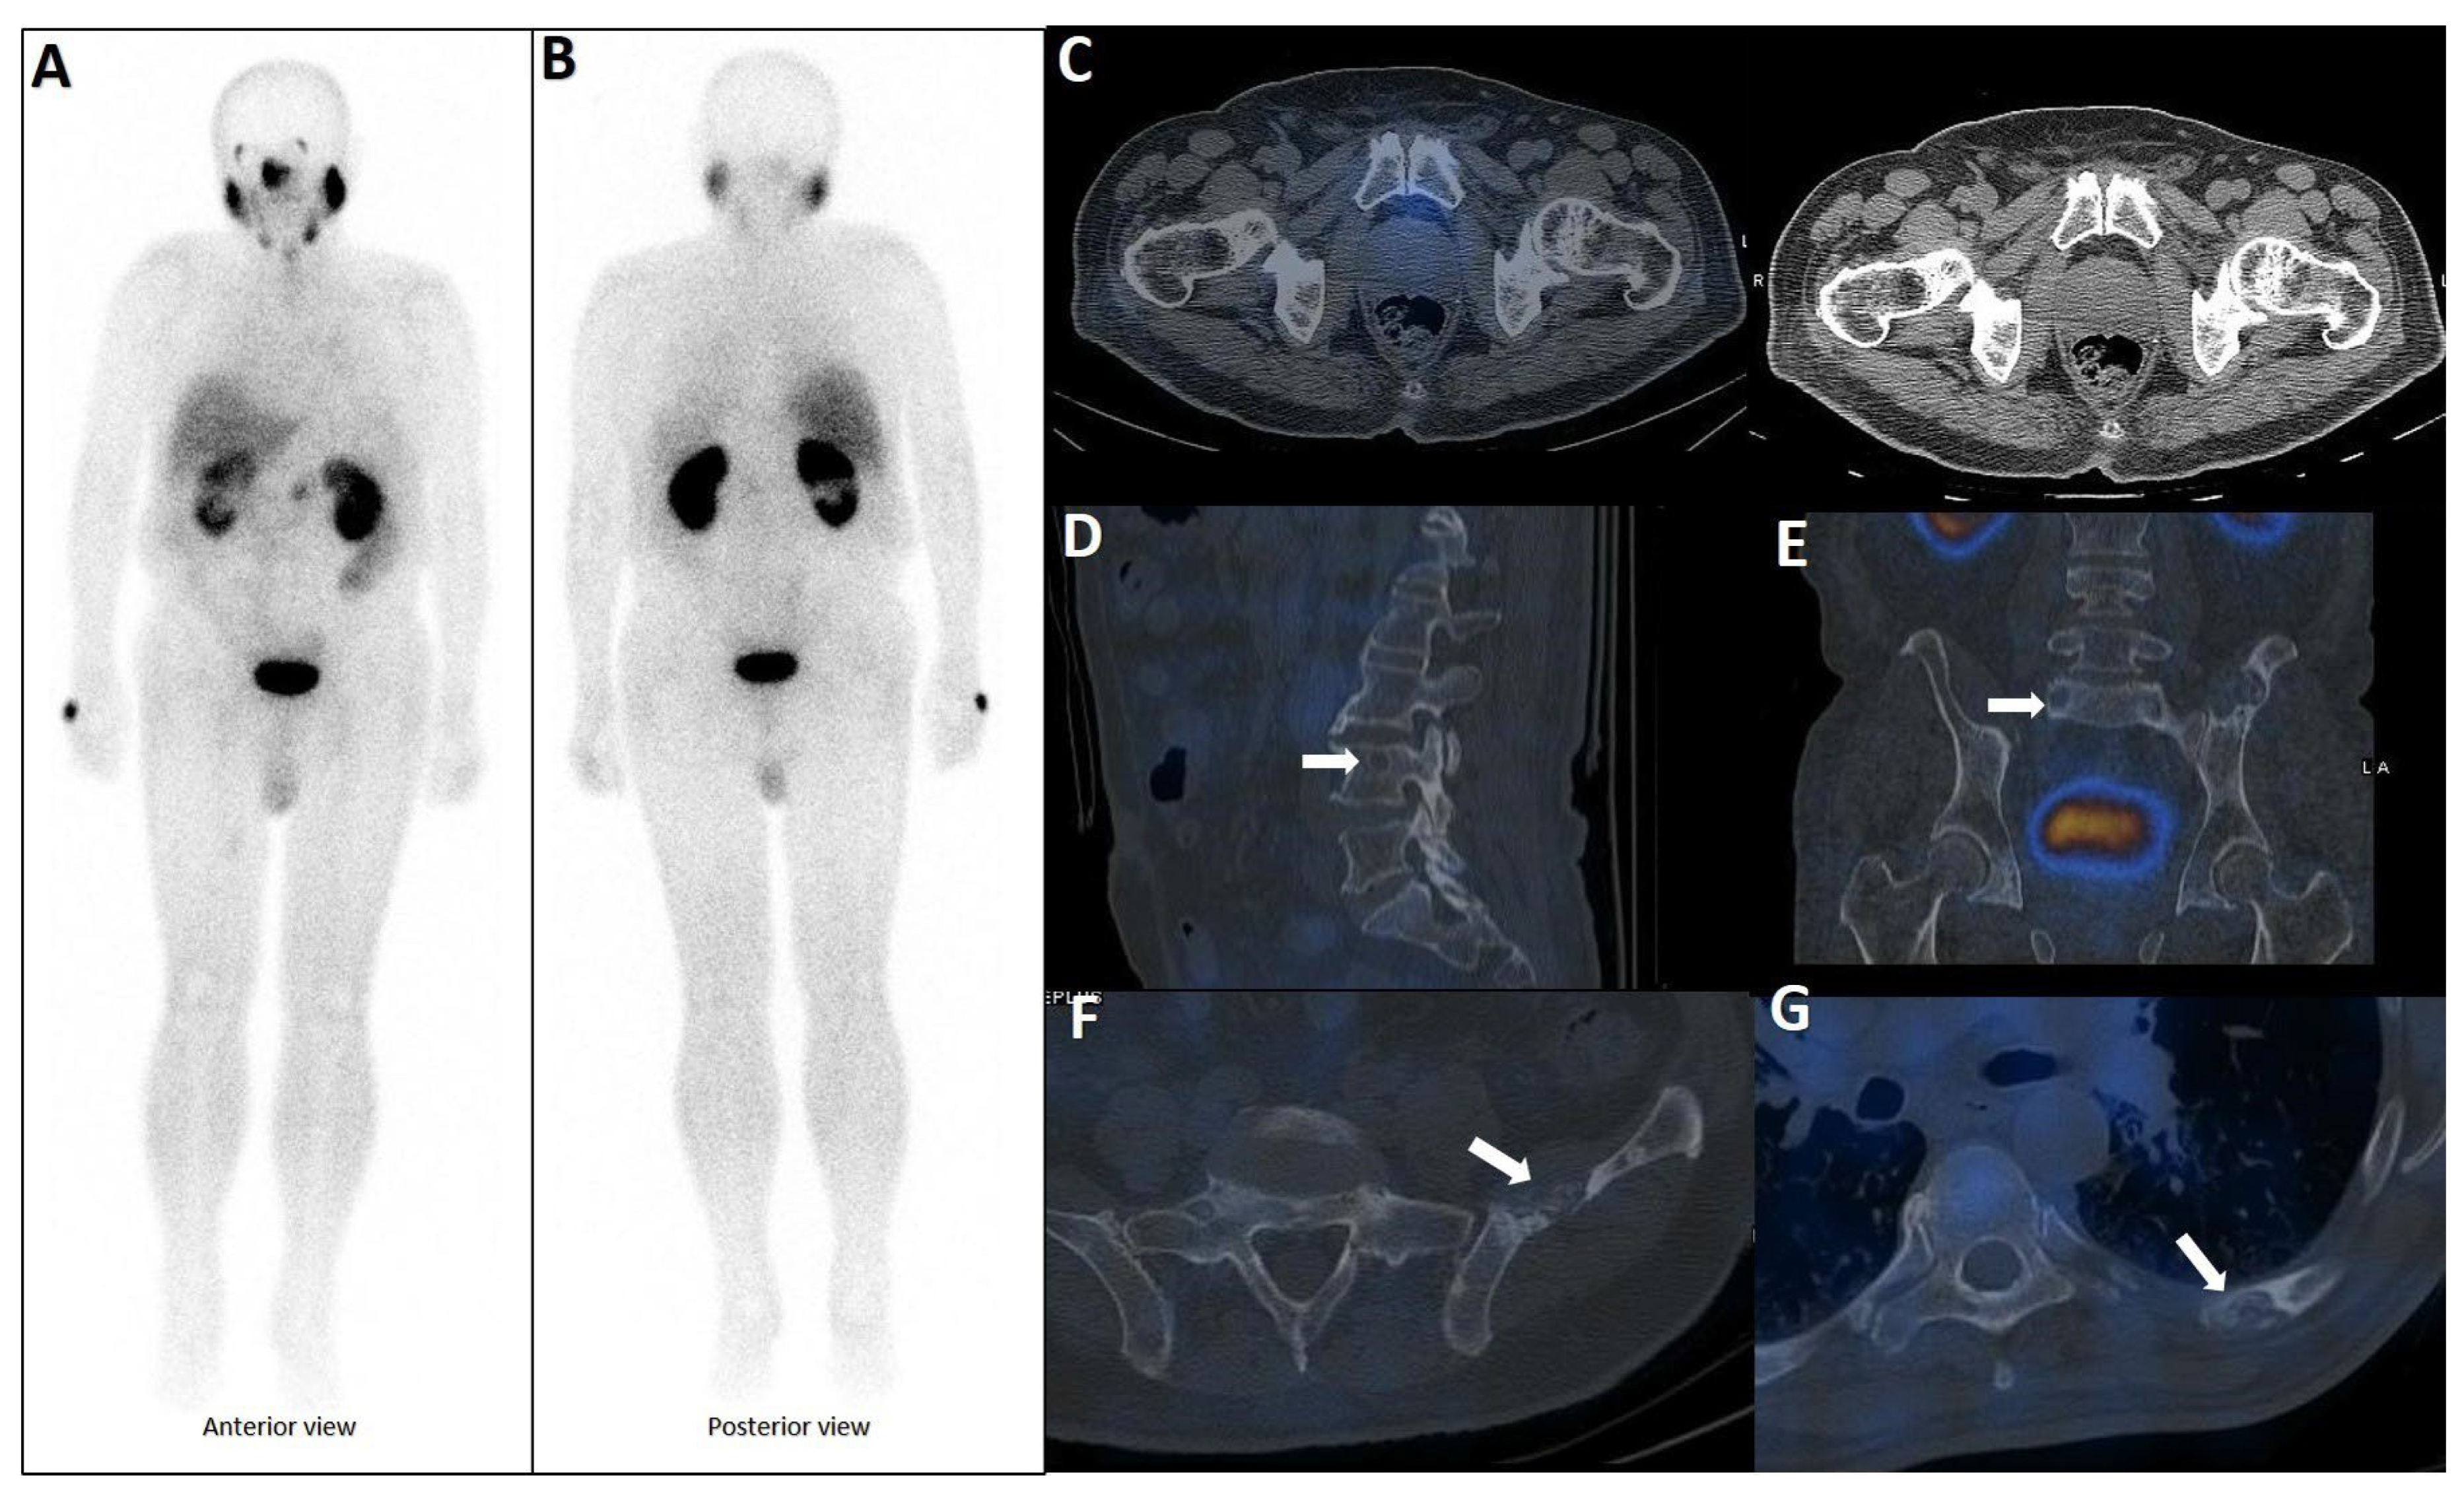

CT is widely utilized for evaluating rib metastases due to its high spatial resolution and capacity to detect cortical destruction, sclerosis, and soft tissue extension (Figure 1). It is particularly effective in identifying osteoblastic lesions, which are common in PCa, and serves as a valuable tool for guiding biopsies. However, CT has notable limitations: it exhibits low sensitivity for detecting early metastatic lesions (those lacking structural changes (Figure 2) and offers limited specificity in differentiating benign findings (e.g., post-traumatic sclerosis) from malignant ones (Figure 3) [8,114,115].

Figure 1.

Spectrum of CT changes in prostate cancer patients, arranged by highest risk of malignancy (A–E). Expansile lytic-destructive lesion with a “soft tissue component”, indicating aggressive variant prostate cancer or concurrent malignancy (A). Sclerotic-destructive metastases with “cortical expansion” (B). Sclerotic metastases showing sun-burst “periosteal reaction” and pathological fracture (C). Sclerotic metastases with “cortical thickening and irregularity” (D). Lytic–sclerotic metastasis featuring “focal small areas of cortical erosion/destruction” (E).

Figure 2.

Early phase of metastases without clear sclerotic changes in the bone. (A) 70-year-old man with elevated PSA was recently diagnosed with prostate adenocarcinoma (all cores positive with Gleason score 5 + 4) and referred for staging. The whole-body 99mTc-PSMA scan (A,B) and SPECT/CT showed multiple PSMA-avid skeletal metastases, most of which showing no/minimal density changes (C–F).

Figure 3.

False positive findings in bone scintigraphy due to rib fractures. A 78-year-old man with prostate adenocarcinoma (biopsy Gleason score 4 + 4, serum PSA = 56.8 ng/mL) was referred for staging. Whole-body bone scan revealed two consecutive focal osteoblastic activities in the lateral arc of the ribs on the right side (A,B). 99mTc-PSMA SPECT/CT (C) revealed increased tracer uptake in the prostate gland (D), multiple metastatic lymphadenopahies on the left side of pelvis and para-aortic regions (red arrow, (E)). Moreover, fractures in the right 6th and 7th ribs showed no PSMA avidity (white arrowheads, (F,G)).